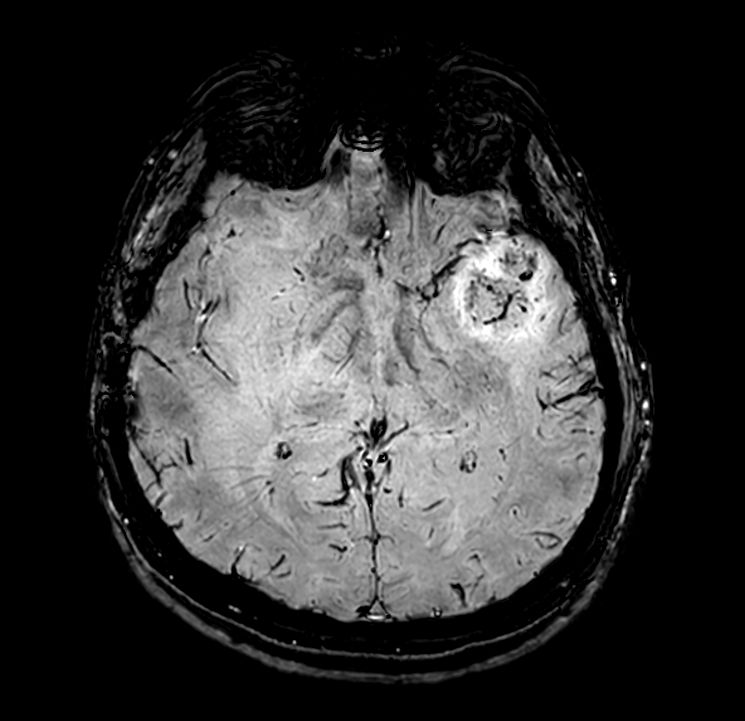

Large lesion brain imaging with synthetic MRI

Patient with a large brain lesion. AI based SmartSpeed is utlized to shorten scan time without compromise in image quality. Advanced imaging techniques like pCASL and 3D APT are used to perform contrast-free brain imaging to assess perfusion and tumoral activity. SWIp 3D susceptibility weighted offers the high sensitivity required to visualize deoxygenated (venous) blood or calcium deposits. A single synthetic (SyntAc) brain quantification scan is added. The resulting data of this scan can be used as input for advanced third party processing software* to synthesize MR images with different contrasts, brain parenchyma fraction maps and/or brain segmentation maps.

Axial SWIp (Modulus)

Axial SWIp (minIP)

Axial SWIp (Phase)